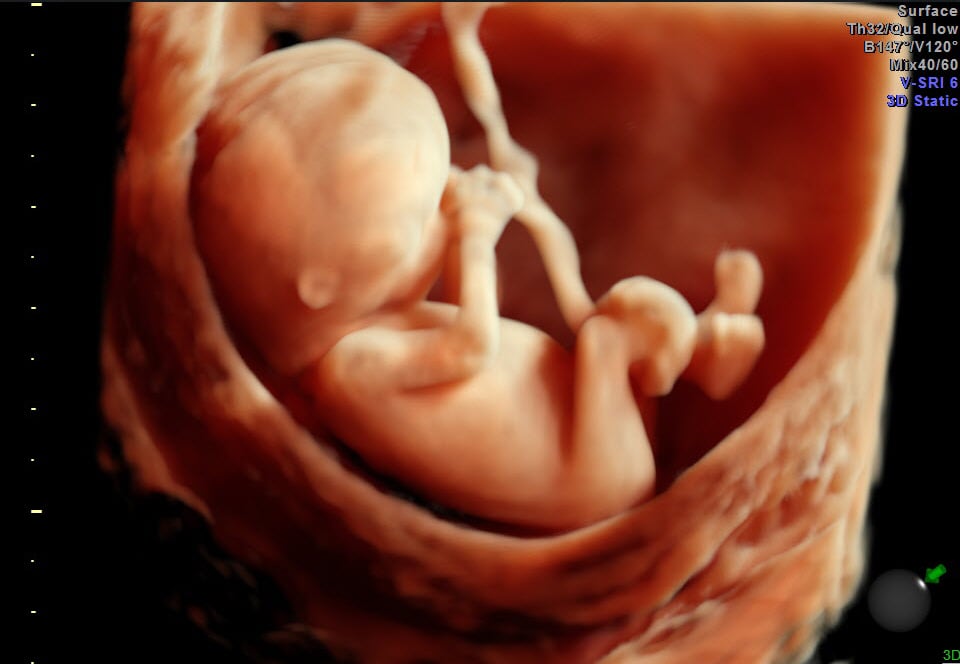

Fetal ultrasound imaging provides real-time images of the fetus. Doppler fetal ultrasound heartbeat monitors are hand-held ultrasound devices that let you listen to the heartbeat of the fetus. Both are prescription devices designed for use by trained healthcare professionals. They are not intended for over-the-counter (OTC) sale or use, and the FDA strongly discourages their use for creating fetal keepsake images and videos.

Fetal keepsake videos are controversial because there is no medical benefit gained from exposing the fetus to ultrasound. FDA is aware of several enterprises in the United States that are commercializing ultrasonic imaging by making fetal keepsake videos. In some cases, the ultrasound machine may be used for as long as an hour to get a video of the fetus.

While FDA recognizes that fetal imaging can promote bonding between the parents and the unborn baby, such opportunities are routinely provided during prenatal care. In creating fetal keepsake videos, there is no control on how long a single imaging session will last, how many sessions will take place, or whether the ultrasound systems will be operated properly. By contrast, Veazy says, “Proper use of ultrasound equipment pursuant to a prescription ensures that pregnant women will receive professional care that contributes to their health and to the health of their babies.”